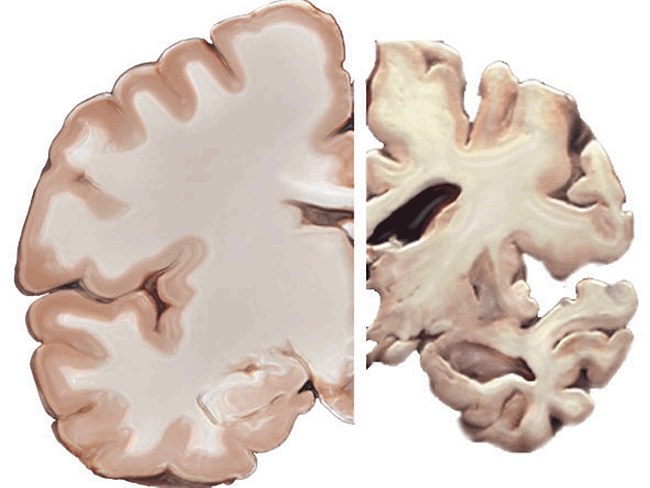

Keeping you up to date on recent developments in diagnostics, including: Automated CT biomarkers predict future CV events; PCR heightens detection of scabies; High BMI linked to dementia via complement component.